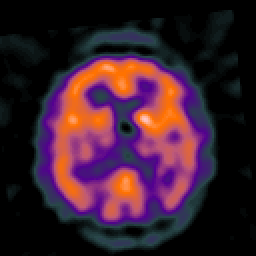

Alzheimer's disease: overlay -- Slice #32

[Home][Help][Clinical] Slice 32